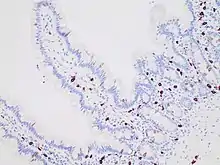

| Micrograph of mastocytosis. Skin biopsy. H&E stain. | |